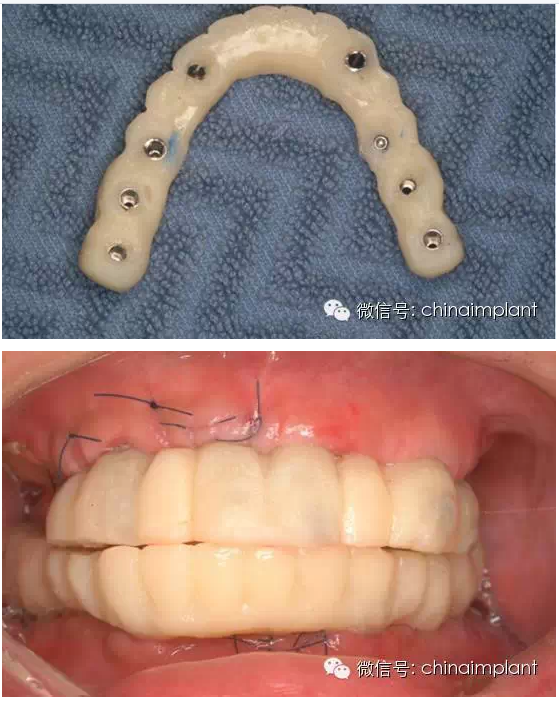

之前針對(duì)全口無(wú)牙進(jìn)行種植修復(fù)的案例中,因?yàn)轭M骨的原因,后期使用橋冠修復(fù)時(shí),一般是3部分(兩側(cè),磨牙,前牙),最近的案例中修復(fù)是一般都是做一體式的橋冠,現(xiàn)在從臨床的修復(fù)案例來(lái)看,沒有什么問(wèn)題。

此案例為術(shù)后兩周戴臨時(shí)牙。過(guò)去因?yàn)閾?dān)心感染的問(wèn)題,一個(gè)月以內(nèi)帶臨時(shí)牙也叫做即刻負(fù)重或者早期負(fù)重。(現(xiàn)在當(dāng)天戴臨時(shí)牙(即刻復(fù)重)的情況也非常常見).